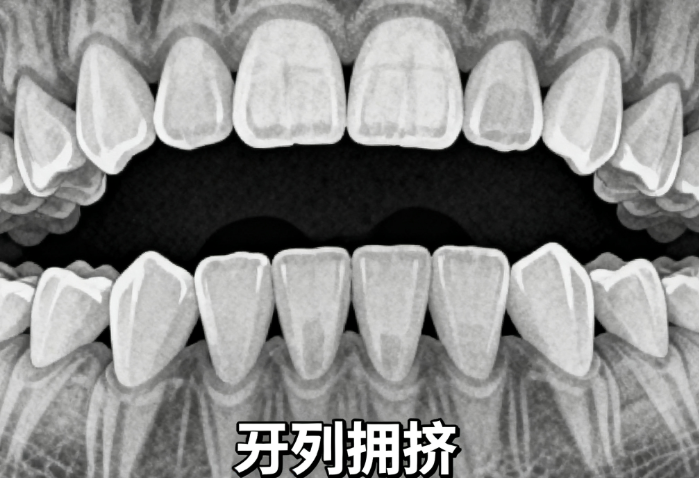

适合人群:3-12岁儿童,有地包天、龅牙等问题